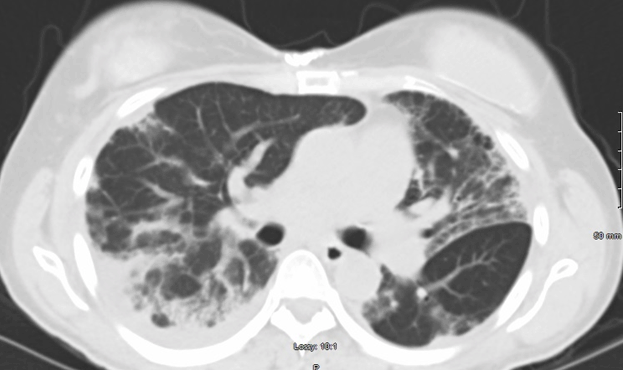

With regards to her pulmonary fibrosis, she was started on Nintedanib 150mg twice daily. Her dyspnea improved, and she was tapered down to 100 mg twice daily. Clinical improvement was mirrored by radiological improvement on computed tomography taken at diagnosis and two years later (Figures 2 and 3). She has been maintained on Mycophenolate 500 mg twice daily and Nintedanib 100mg twice daily for over two years without significant relapse. Malignancy screening including computed tomography of the chest, mammogram, pap smear, and colonoscopy were negative.

Figure 3: Computed tomography of the chest without contrast, 2 years later after being started on Nintedanib, along with 6 months of Cyclophosphamide induction and concurrent Mycophenolate. She is currently maintained on Nintedanib and Mycophenolate.